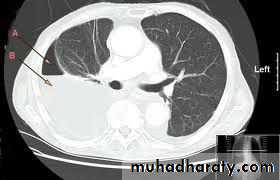

1. CXR 2. CT scan

1) well defined circular or oval homogenous opacity

thoracic surgery

2) perivesicular pneumocyst or signet ring sign